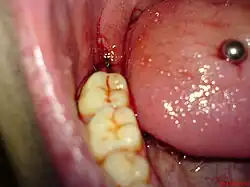

Das Missverhältnis zwischen Kiefergröße und Zahnanzahl führt am Kieferwinkel, dem Übergang vom horizontalen zum aufsteigenden Ast des Unterkiefers dazu, dass sie häufig keinen ausreichenden Platz mehr finden und vollständig retiniert bleiben oder nur unvollständig durchbrechen (Teilretention). Vollständig retinierte Zähne bleiben normalerweise symptomlos, teilretinierte führen hingegen oft zu Entzündungen (siehe: Dentitio difficilis), die sich zu Abszessen entwickeln können. Ursache für eine solche Entzündung ist die Bildung einer kapuzenförmigen Zahnfleischtasche (Operculum), die nur schwer oder gar nicht gereinigt werden kann. Bakterien können sich in dieser Tasche mit Hilfe von sich zersetzenden Speiseresten schnell vermehren. Das Operkulum kann in einem kleinen chirurgischen Eingriff namens Operkulektomie entfernt werden, der es erleichtert, den Zahn zu reinigen. Auch kann Karies begünstigt werden, wenn Weisheitszähne so an einem Nachbarzahn anliegen, dass dort nur schwer geputzt werden kann.